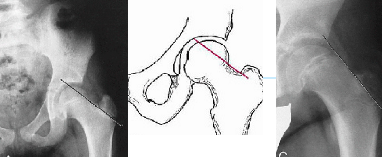

Q what is the name of this measurement? and what is the average + range?

A: Meyerding's Grading Method

assesses the degree of spondylolisthesis.

The superior surface of the sacrum is divided into four equal parts to quantify the degree of forward slippage of the Posteroinferior corner of L5.

A: Ullmann's Line

assesses for spondylolisthesis by evaluating the position of L5 relative to a perpendicular line. No average or range is specified.

A: Van Akkerveekans measurement of Lumbar instability

assesses lumbar instability by measuring horizontal displacement. There should be less than 1.5 mm of displacement.